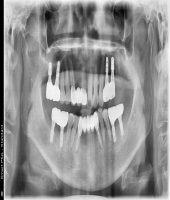

| ● 진료과목 : [임플란트] 틀니 사용중, 임플란트로 교체하기

| ● 내용 : 하악틀니 사용 중 불편감으로 임플란트로 교체한 예 |